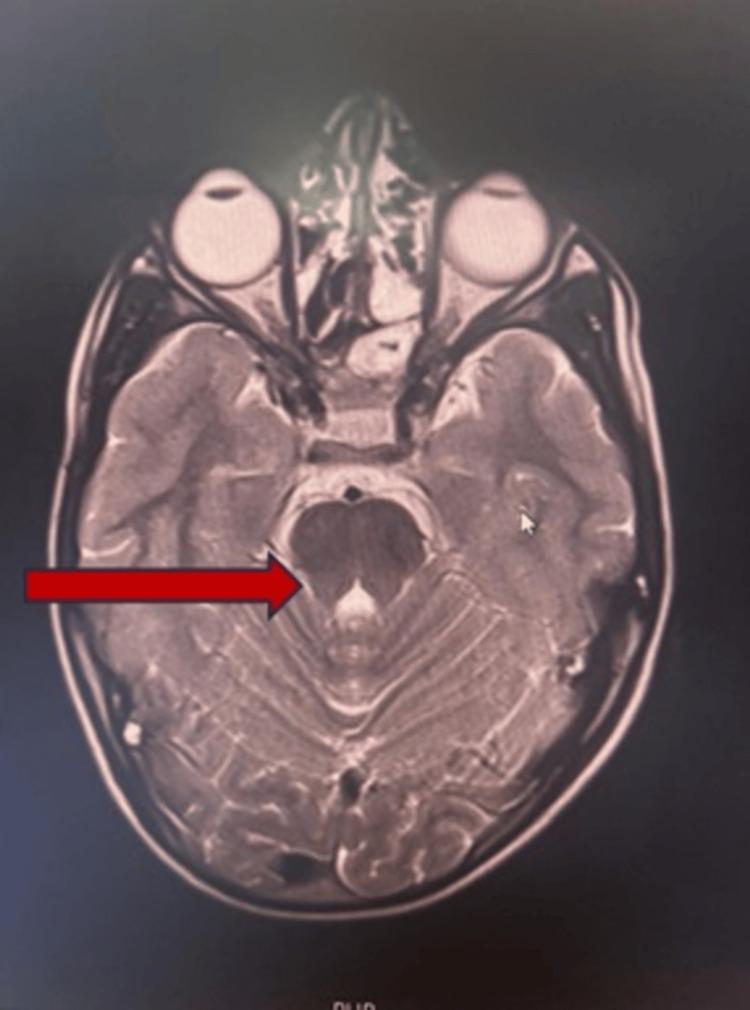

Horizontal gaze palsy with progressive scoliosis (HGPPS) is a rare autosomal recessive disease associated with mutation in the Roundabout-3 (ROBO3) gene (chromosome 11q23-25). Here, we present case report of a 7-year old male child born out of consanguineous marriage with history of similar condition in paternal uncle. The child had typical findings of HGPPS, i.e., horizontal gaze palsy, scoliosis, and characteristic findings on MRI associated with homozygous c.575G>A (p.Gly192Asp) mutation in ROBO3 gene. Additionally, mutation in G6PD gene was also observed in this patient, hypothesizing possible association between the two.

伴有进行性脊柱侧凸的水平凝视麻痹(HGPPS)是一种罕见的常染色体隐性疾病,与轴突导向分子-3(ROBO3)基因(位于11号染色体q23 - 25区域)突变相关。在此,我们报告一例7岁男性患儿,其父母为近亲结婚,患儿的叔祖父有类似病史。该患儿具有HGPPS的典型表现,即水平凝视麻痹、脊柱侧凸,且MRI有特征性表现,同时ROBO3基因存在纯合的c.575G>A(p.Gly192Asp)突变。此外,该患者还检测到葡萄糖-6-磷酸脱氢酶(G6PD)基因的突变,推测二者可能存在关联。